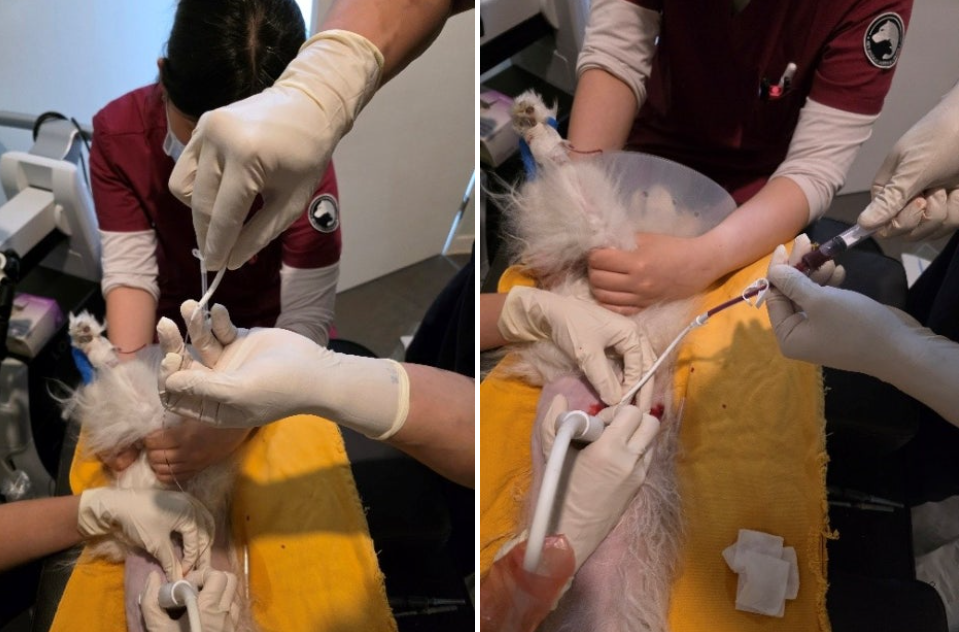

이러한 판단으로 초음파 유도 하에 pigtail catheter를 삽입하여 지속적인 배액을 시행하였습니다.

이후 환자는 점진적인 임상적 호전을 보였습니다.